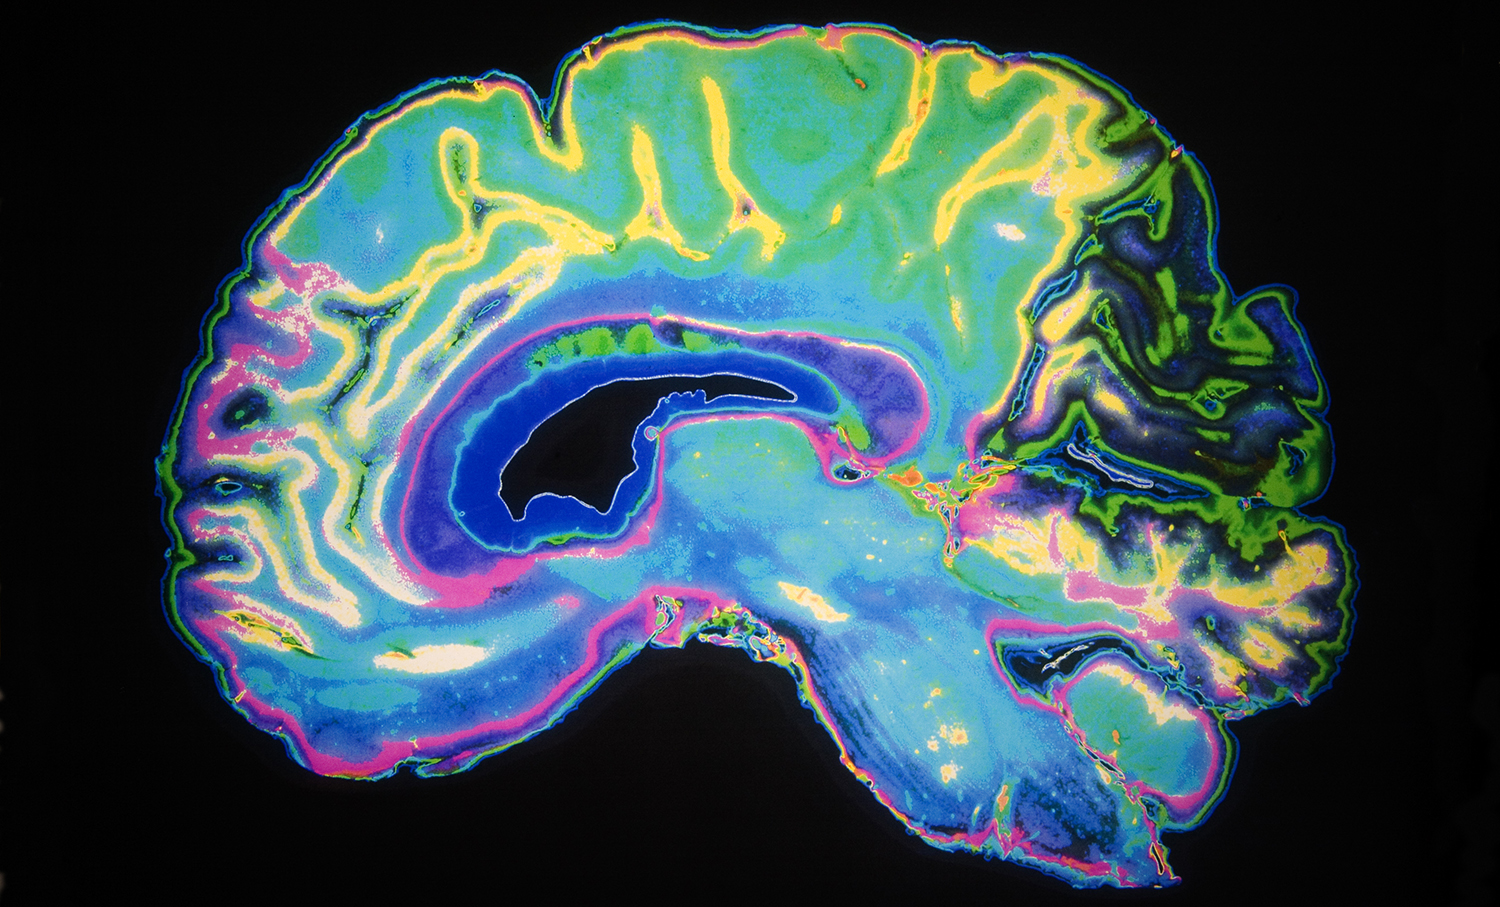

Denne aften har vi samlet fire eksperter, der skal berette om nogle af de nyeste og mest interessante resultater af forskningen i psykedeliske stoffer. Det indbefatter studier af, hvad der rent faktisk sker i hjernen, når man indtager psykedelika og andre euforiserende rusmidler såsom cannabis, og i hvilke sammenhænge stofferne har gavnlige medicinske virkninger. Desuden skal vi høre om praktiske erfaringer med brugen af medicinsk cannabis til smertebehandling. Og så skal det handle om ‘psykedelisk medicin fra naturen’ set fra et etnobotanisk perspektiv.